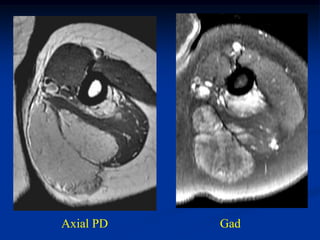

Case #1191

24 year female with

angiolipoma anterior

thigh

Sagittal T-1 MRI

Axial T-1 MRI

Coronal T-2 MRI

Sagittal gad

contrast MRI

Case #1191 24 yearfemale with angiolipoma anterior thigh Sagittal T-1 MRI

• 90.

• 91.

• 92.